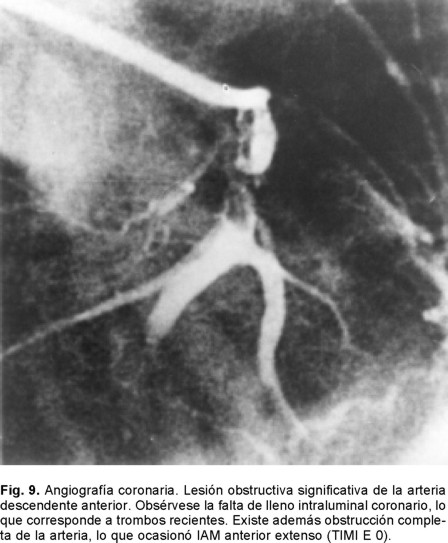

Lo más trascendente es que nos obliga a abrir la mente en aspectos terapéuticos que antes no se consideraban relevantes en la clínica. Tal es el caso al referirnos a los procedimientos más utilizados hoy día para resolver la problemática de arterias epicárdicas ocluidas en el infarto agudo del miocardio o parcialmente obliteradas como en la angina inestable. Si bien la primera meta de la reperfusión en el IAM ha sido obtener flujo TIMI - 3 epicárdico, ésta no parece ser hoy día el solo punto terapéutico final deseado.111 Ya que lo que es óptimo es alcanzar también una perfusión normal a nivel miocárdico y que incluye como premisa la permeabilidad completa de la microcirculación, para entonces decir que se alcanzó flujo TIMI - 4 o miocárdico. Ésta es una de las razones por la que con los métodos modernos de reperfusión no es posible reducir la mortalidad del IAM a cifras cercanas al cero. Con los comentarios hechos previamente también queda claro que hay otros aspectos que están vinculados a la propia reperfusión: el daño ocasionado por ésta, el fenómeno de no flujo, el miocardio aturdido, el hibernante y aspectos aún desconocidos como es la consecuencia de liberar la propia obstrucción microvascular. Patologías isquémicas que tienen un punto inicial de partida: la placa aterosclerosa vulnerable que sufre erosión o fractura (Fig. 4). Situación que deja expuesta la matriz subendotelial y en donde su principal contenido de masa oclusiva es la plaqueta [trombo blanco], mas hay trombosis también donde predominan los glóbulos rojos, con oclusión completa o subtotal en un proceso no estático en sus componentes y que a su vez da origen a los síndromes coronarios agudos de infarto con o sin elevación del segmento ST.109 Es así como en su evolución se ha identificado el fenómeno de la microembolización con alojamiento de estos fragmentos plaquetarios y del contenido de la matriz en los microvasos coronarios distales, proceso que antes se consideraba como una condición no frecuente. Este mecanismo se ha vinculado como una de las posibles causas por la que se generan arritmias y es causa de episodios de muerte súbita.107,108 Es de llamar la atención que no hay muchos estudios importantes donde el área histológica relacionada con el infarto se ha investigado sistemáticamente en el post mortem de estos sujetos. Aspecto que se puede considerar como una deficiencia en nuestros conocimientos actuales, particularmente cuando la terapia trombolítica o la de reperfusión de la ARI con catéteres son nuestros principales métodos terapéuticos para la atención del IAM y ambos son capaces de promover la embolización (Fig. 5). Los PCI se iniciaron hace más de dos décadas y durante todo este tiempo hemos subestimado la posibilidad de que esta situación patológica o bien se le ha considerado muy rara o sólo era conferida al terreno de los injertos de safena añosos y degenerados cuando éstos eran manipulados con catéteres.112 Porqué no nos hemos hecho la pregunta antes: ¿qué sucede con el material de la placa ateromatosa al ser instrumentada? En realidad es hasta hace poco que la opinión de lo raro o lo frecuente de la posibilidad de embolización a la microcirculación ha sido posible contestarla y poder decir si en realidad esta situación derivada del manejo medicamentoso farmacológico o del intervencionismo es trascendente, o bien es irrelevante.

Sabemos que hace 70 años la mortalidad del IAM era cercana al 40%, misma que se logró reducir al 25% a principios de 1951 con la simple maniobra de la movilización temprana y al 20% con la creación de las Unidades Coronarias en 1973. Es en 1987, con la introducción de la terapia fibrinolítica que se establece un nuevo descenso para considerarse cercana al 8%. Ya perfeccionada la terapia de reperfusión y con la introducción de los PCI (angioplastía con balón y mallas endovasculares coronarias) es que tenemos un resultado que oscila del 4 al 6% de mortalidad del IAM (Fig. 10). Es por eso que hoy día se acepta que esta modalidad terapéutica es la que ha sido capaz de brindar el más importante descenso de la mortalidad en el rubro del IAM transmural. Entre los factores más importantes de los que depende alcanzar esta reducción está el factor tiempo relacionado al momento en el que se de el tratamiento o ventana terapéutica en la que se aplique la terapia de reperfusión. La magnitud de miocardio salvado determinada experimentalmente para el ventrículo izquierdo es cercano al 70% si la reperfusión se realiza en la primera hora a partir de haberse ocluido la arteria epicárdica. Disminuye al 40% a la tercera y al 20% a la sexta, para ser menor del 5% a las 24 horas. Para el ventrículo derecho Lester y colaboradores124 han encontrado que el área de infarto a la hora de reperfusión es de tan sólo un cinco por ciento, a las cuatro horas es de un 10% y a las ocho es del 20%. Por lo tanto, el acortar el tiempo de la reperfusión para cualquiera de ambas cámaras ventriculares sería igual a menor daño miocárdico o mayor magnitud de miocardio salvado. Esta es una de las razones por la que después de seis horas el beneficio de la reperfusión de la arteria epicárdica decae significativamente para considerarla casi nula después de doce horas. Lo que se aplica tanto para el tratamiento fibrinolítico como para los PCI. Si en la ARI no se obtiene permeabilidad inmediata la mortalidad es del 17.5%, lo que equivale a remontarnos a la consignada en los años de 1970. Si la ARI está permeable a los 90 minutos pero se le encuentra ocluida al séptimo día, la mortalidad es del 12% lo cual nos ubica en la mortalidad documentada a principios de 1980. Si la ARI está permeable a los 90 minutos y al séptimo día la mortalidad es del 4.7%. Por otro lado, la importancia de la calidad del flujo epicárdico post reperfusión resulta extraordinariamente relevante. Las primeras observaciones en este sentido con la terapia de reperfusión lítica nos demostraron que cuando el flujo epicárdico es TIMI: 0 -1 la mortalidad del IAM es del 8.9%, al ser grado TIMI: 2 la mortalidad es del 7.4% y con TIMI: 3 epicárdico es del 4.4% (Figs. 8 y 11 A - 11 B). Pero por fortuna hemos avanzado en el conocimiento en este sentido y con la valiosa información del estudio GUSTO II b (The Global Use of Strategies to open Occluded Coronary Arteries in Acute Coronary Syndromes) sabemos que con ACTP de obtenerse flujo TIMI 0-1-2 la mortalidad es del 18 - 20%, cifras que resultan casi del doble de las documentadas con trombólisis para los mismos flujos, hecho interesante que nunca se ha explicado claramente.125 En cambio de obtenerse flujo TIMI 3E la mortalidad a treinta días es de tan sólo 1.6%, observándose menor tamaño del área infartada y mayor índice de miocardio salvado. Lo que establece sólo una diferencia del 2.8% entre las dos estrategias de reperfusión cuando se alcanzan flujos TIMI 3E (Fig. 8). Para llegar a estas conclusiones, frente a los enfermos es menester tomar en consideración los datos relevantes proporcionados por Gibson y colaboradores en relación al análisis angiográfico de la perfusión miocárdica.126 Mismo que se ha valorado por dos métodos pero que al final sólo traducen que existe perfusión a nivel de la microvasculatura. Empero hay que recordar que existen varios factores de los que también depende el flujo TIMI epicárdico como son los de orden: hemodinámico, la anatomía local de la arteria, la propia técnica del procedimiento, el trombo intracoronario y aspectos derivados del intervencionismo: la estenosis residual, la disección involuntaria de la arteria coronaria y menos relevantes parecen la aplicación de las mallas endocoronarias (Fig. 12).126 Excluidas estas causales, quedarían las dos más importantes a considerar: la obstrucción microvascular y las que son producto del fenómeno de no flujo en la microcirculación. El flujo TIMI en la microcirculación se expresa o se visualiza en la angiografía coronaria como áreas de condensación de aspecto esmerilado muy finas del material de contraste a nivel del miocardio. Esto es lo que los autores anglosajones designan en su lengua como "blush" y que correspondería a "TIMI miocárdico 4".127-130 Si bien las anomalías de la microcirculación se han demostrado de manera fehaciente por los diferentes métodos citados con antelación, si se cuestiona si lo que documentamos es también producto de edema miocárdico y/o del daño por reperfusión. Sin embargo este patrón de alteración microcirculatoria ocurre tempranamente (en las primeras horas o días), lo que hace menos probable que sea por daño por reperfusión. Es más, se le ha documentado en sujetos que van a PCI (rotaablación coronaria) y tras la práctica de ellos aparecen cambios miocárdicos en los estudios de perfusión nuclear, lo que sugiere embolización a la microcirculación (Fig. 13). 121,122 Con la utilización de catéteres con redes o sistemas de aspiración se han recuperado fragmentos del material que hubiesen sido embolizados. Por lo tanto, en la clínica se puede decir que este mecanismo se sugiere como la causa primordial, al menos en etapas tempranas, de las anomalías documentadas en la microcirculación. Mas es innegable que en el caso de IAM transmural reperfundido deberán estar presentes los dos mecanismos, el inicial ligado a la microembolización y el tardío aunado a los fenómenos de la injuria post reperfusión (Fig. 5). Lo importante es que la obstrucción microvascular está vinculada a mal pronóstico aún de obtenerse la permeabilidad deseada de la arteria epicárdica. Wu y colaboradores131 han demostrado que a 25 meses el 90% de los enfermos sin OMV están libres de muerte-reinfarto e insuficiencia cardiaca. De existir OMV tan sólo el 55% lo estarán. Es más, con estudios de resonancia magnética nuclear se ha podido catalogar la magnitud de los defectos en áreas grandes, moderadas y pequeñas de OMV con diferencias estadísticas en morbimortalidad de cada una de estos grupos y directamente proporcionales a la magnitud del defecto documentado en la resonancia magnética nuclear. Uno de los primeros estudios en llamar la atención en la posibilidad de microembolización ligada a PCI fue el CAVEAT (Coronary Angioplasty Versus Excisional Atherectomy) donde la incidencia de IAM fue superior a la esperada. Se encontró una frecuencia de IAM del 3% para ACPT y del 6% para aterectomía rotacional. En este estudio prospectivo la elevación de la CK-MB a cifras tres veces por arriba del valor basal fue de 8% para la ACTP y del 19% para la aterectomía.121 En el estudio CAVEAT II sobre intervenciones en libramientos de venas safenas la incidencia de IAM fue considerablemente mayor 15 y 24% respectivamente.122 En nuestro medio Vallejo E y colaboradores132 revisaron 204 angioplastías electivas y 62 primarias. El fenómeno de no flujo predominó en hombres, con edad promedio de 56 años y fue la diabetes mellitus un factor de mayor riesgo para observarlo. La incidencia global del problema fue del 5.2%, 16.1% para la angioplastía primaria y del 1.9% en los procedimientos intervencionistas electivos. Por lo tanto, los autores no la consideran como una complicación rara o infrecuente particularmente en el escenario del IAM. Este importante hallazgo de todos los estudios previamente mencionados dio origen a ciertos debates, si los procedimientos intervencionistas utilizados creaban fuga enzimática, eran capaces de dar seudoinfartos o microinfartos.66 En el seguimiento a largo plazo se demostró un exceso de mortalidad para la aterectomía y aquellos que fallecieron presentaron durante el procedimiento cambios dinámicos del segmento ST muy sugestivos de IAM no transmural o subendocárdico. Varios estudios posteriores han demostrado que a mayor elevación de la CK-MB post PCI hay mayor probabilidad de muerte.121,122 Así cuando la elevación de CK-MB es de cinco veces el valor basal, la mortalidad al año es de 6 -7%, de ser 10 veces el incremento de CK-MB es del 13%. La posible causa de este hallazgo es la microembolización coronaria ya que otras eventualidades son menos frecuentes o resultan menos probables como factores causales tales como el tiempo de isquemia ocasionado por el balón que es habitualmente demasiado corto para ocasionar necrosis per se. Las oclusiones abruptas de ramas coronarias epicárdicas hoy día son poco frecuentes (< 3%) y la oclusión sú bita coronaria transitoria se le ve en menos del 1%.135 La incidencia por lo tanto de grados diversos de micromionecrosis, consecuencia de la embolización coronaria, al menos significativa no parece despreciable. Valorada utilizando biomarcadores como la Troponina T o I parece cercana al 30 - 40%. Si bien la identificación alta de troponinas post intervención parece importante, también lo es cuando se documentan elevaciones de la misma antes de realizar los PCI.136,137 Así Hamm y cols138 han demostrado que hay una respuesta diferente al tratamiento con bloqueadores de los receptores plaquetarios. Aquellos con Troponina T positiva al ingreso responden favorablemente al inhibidor del receptor plaquetario por el bloqueo del mecanismo citado a nivel de la microcirculación, además de reducir la frecuencia del trombo en la arteria epicárdica sometida a ACTP o a la colocación del stent.